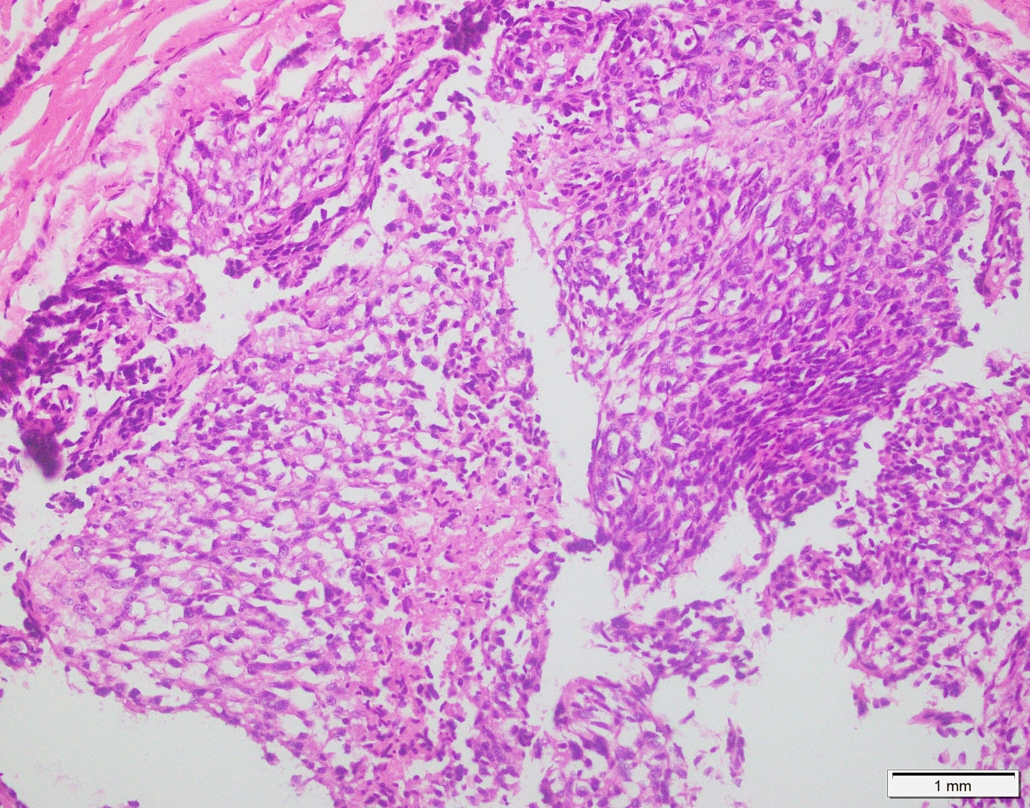

Case 03

Case presented by Dr Shaarif Bashir, FCPS (PAK), Shaukat Khanum Memorial Cancer Hospital and Reserach Centre, Pakistan